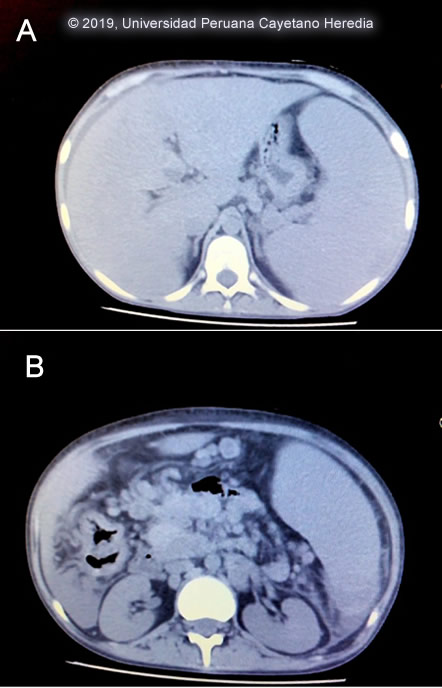

The chest x-ray showed bilateral interstitial infiltrates that were corroborated in the chest CT-scan [Image A]. An abdominal CT-scan showed visceromegaly [Image B]. A colonoscopy was performed, multiple colonic ulcers were observed scattered over the entire colon and ileum [Image C]. UPCH Case Editors: Carlos Seas, Course Director / Carlos McFarlane, Associate Coordinator UAB Case Editor: David O. Freedman, Course Director Emeritus / German Henostroza, Course Director |